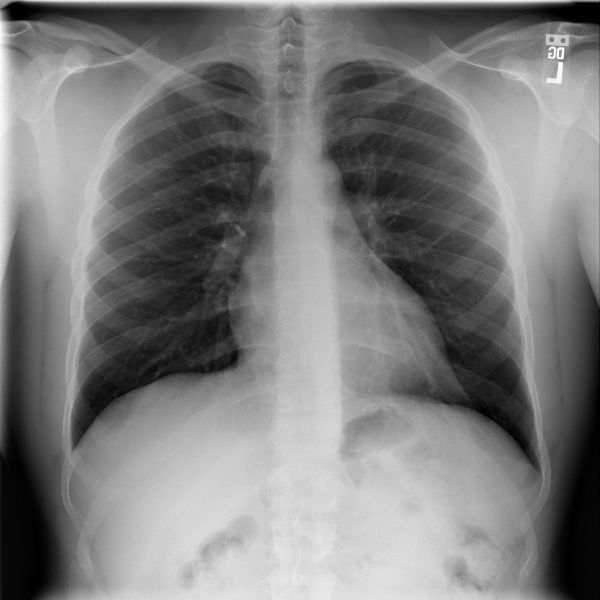

2 Backends

Figure 3: From left to right: A chest X-Ray from the COVID-19 image data collection [5], a lung CT slice also from [5] and 3D prostate CT image from the Medical Decathlon dataset [6]